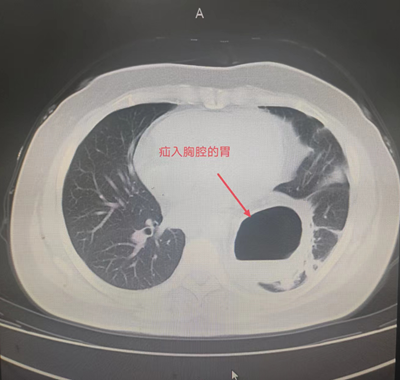

患者辛某,今年85岁,1年前患者因反酸、进食后反复呕吐于外院就诊。胸腹部CT检查提示:膈疝。胃十二指肠镜检查提示:食管外压性改变,膈疝,食管裂孔疝。患者长期营养不良,无法经口进食,只能通过鼻饲-空肠营养管置入进行营养,近日因营养管再次出现导管堵塞,随后被家人紧急送往21点策略指南站 住院治疗。住院后进一步检查诊断食管裂孔疝、肺部感染,既往患有脐疝、胸椎手术史,合并心律失常、低氧血症、代谢性酸中毒、肺大疱、心脏瓣膜疾病、左侧颈动脉斑块形成、腔隙性脑梗塞等老年病史。

由于患者年事已高,病情复杂,手术难度极高。普外科主任田德福充分考虑到患者年龄、病情实际,先组织科室任斌、尹超、杨洲明、何慢等专家进行危重症患者治疗方案讨论。随后联系医务科组织全院多学科MDT讨论,根据全院MDT多科室会诊结果制定了周密的手术计划,并针对高龄患者可能出现的并发症做好各类突发应急准备。在麻醉手术部、手术室的全力配合下,普外科专家团队在全麻腹腔镜下成功为老人实施了食管裂孔疝、膈疝、脐疝三疝同时手术,术中探及食管裂孔疝,直径约4cm,其旁左侧直径约7cm大小膈疝,食管裂孔疝内容物为小网膜组织,膈疝内容物为胃底、胃体大部及大网膜组织。脐疝直径约3cm大小。腹腔镜下进行食管裂孔疝、膈疝无张力修补及脐疝修补术。手术顺利,术中患者生命体征基本稳定。术后在全科医护人员的治疗和精心护理下,逐渐进行经口进流食、半流食。床上活动、渐下床活动。复查各项指标渐正常。胃肠功能恢复正常,于6月14日痊愈出院,近日回访患者一般情况良好。